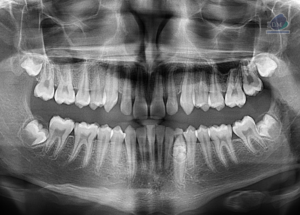

Paciente femenina de 36 años, es referido al Instituto de Diagnóstico Maxilofacial – IDM (Sede Surco) para evaluación de pieza 46 con tratamiento endodóntico. Radiografia